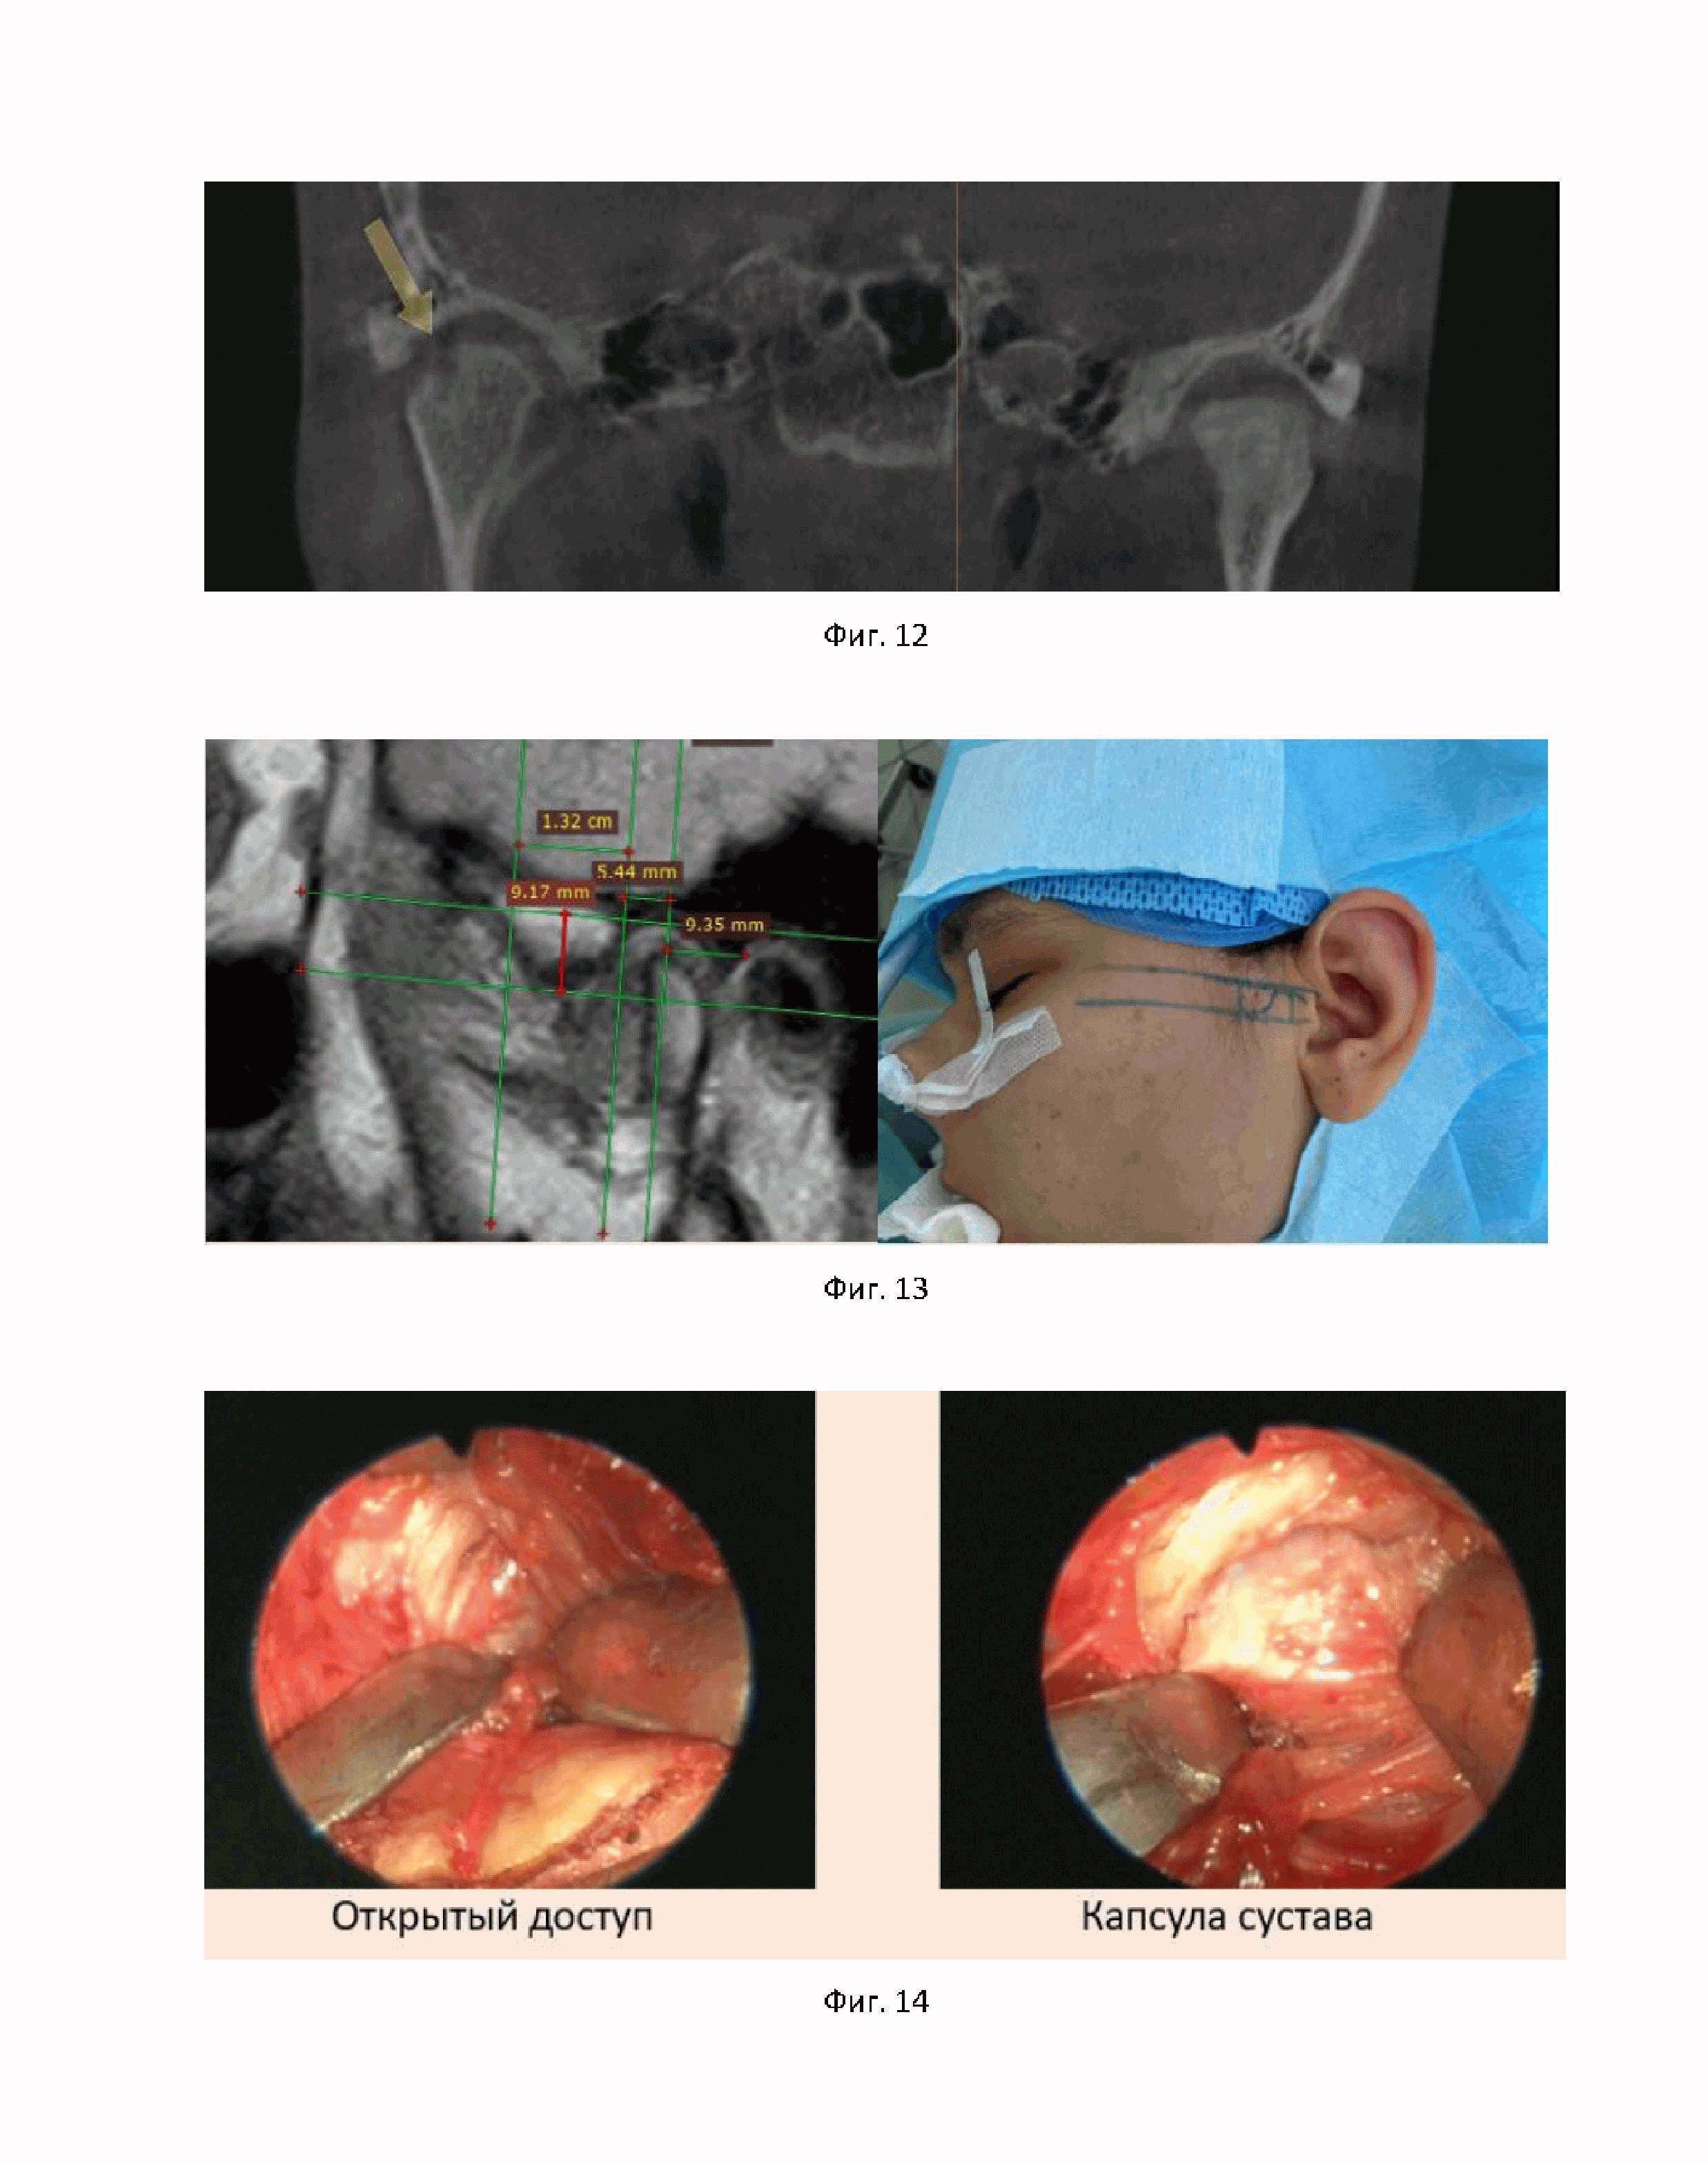

На фиг. 12 показаны результаты магнитно-резонансной томографии ВНЧС для второго примера достижения технического результата.

На фиг. 13 показаны результаты нанесения предоперационной разметки для второго примера достижения технического результата.

Перед операцией МРТ пациентки измерялось. Согласно полученным измерениям, на кожу была нанесена предоперационная разметка (фиг. 13).

Далее была произведена установка артроскопических инструментов согласно данным разметки МРТ, а также рассечение мягких тканей и капсулы ВНЧС малоинвазивным предушным доступом (фиг. 14). Визуализированы внутрисуставные элементы ВНЧС (фиг. 15).